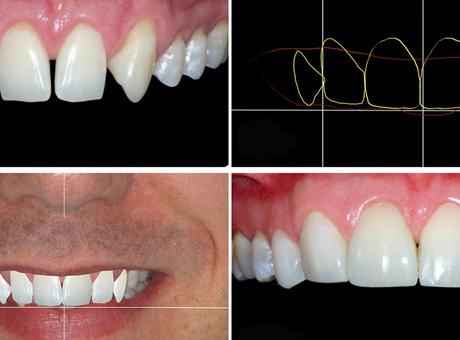

Planejamento digital é arma em prol do sorriso perfeito

Já é possível ter uma prévia de como ficará o sorriso depois de um tratamento de reabilitação oral. O planejamento digital é um recurso que ajuda o dentista a projetar como ficarão os dentes de um paciente. Para isso, o profissional usa fotografias do rosto e do sorriso, que, em seguida, passam por softwares que […]